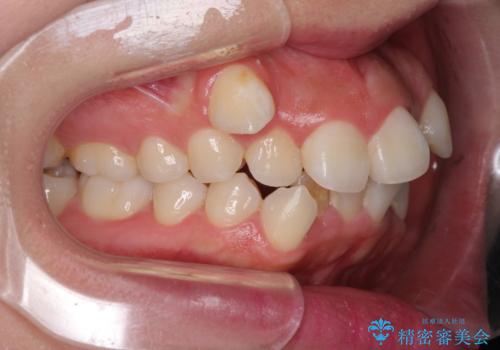

著しい叢生と顎骨のズレ ワイヤー装置による抜歯矯正

- 前歯の著しい叢生や八重歯を気にして来院された患者様です。

上下の顎がずれており、上下の正中は歯1本分の差がありました。

上下左右の小臼歯4本を抜歯し、極力正中を合わせるように矯正治療を始めていくこととしました。